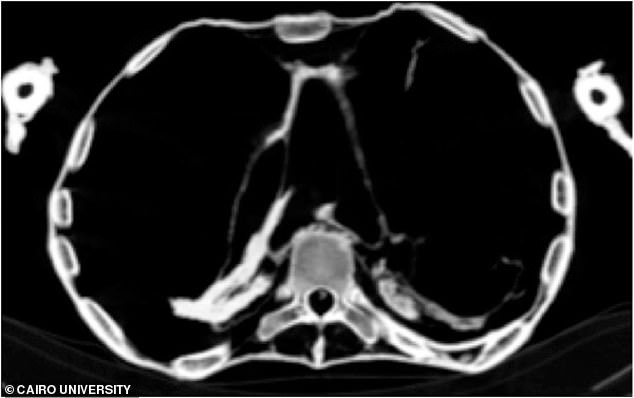

Các nhà Ai Cập học từ Đại học Cairo (Ai Cập) đã sử dụng kỹ thuật CT scan để tìm ra nguyên nhân cái chết và tư thế đầy đau khổ của người đàn bà Ai Cập cổ đại và phát hiện ra rằng nàng đã qua đời vì một cơn đau tim cấp. Tình trạng xơ vữa động mạch vẫn thể hiện khá rõ nhờ kỹ thuật ướp xác danh tiếng của người Ai Cập cổ đại.

Các hình ảnh CT scan cho thấy "công chúa la hét" bị một cơn đau tim cấp do xơ vữa động mạch lâu ngày. Ảnh: Đại học Cairo